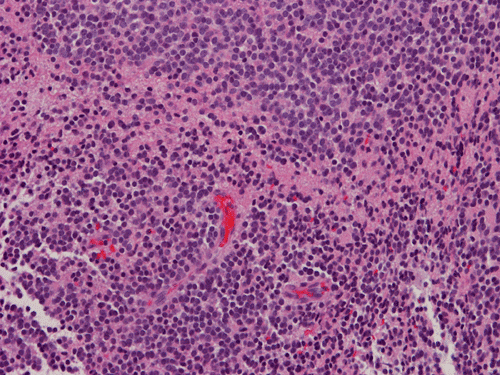

Pathology of the Case: The tumor is composed of neoplastic small blue cells on the cytologic preparation (Pancel C and D) with only minimal amount of cytoplasm. On frozen section (Panel E and F), the tumor cells are packed in solid sheets without specific pattern of arrangement. On permanent sections, the tumor again is composed of solid sheets of small blue cell tumors with rather monotonous nuclei (Panel G and H). In some areas, there is some small neuropil islands (Panel I). No distinct perivascular coronary arrangement is noted.  (Panel J). There is a moderate labeling index on Ki67 (Panel K). The tumor cells are strongly positive for neurofilament proteins (Panel L). Some large stellate, cells positive for glial fibrillary acidic protein (GFAP) are also present and these cells may represent reactive astrocytes (Panel M).

In essence, PPTID is composed of diffuse sheets or large lobules of  uniform cells with mild to moderate nuclear atypia and low to moderate levels of mitotic activity.  Differentiation of grade II and III tumors can be made based upon a combination of mitotic activity levels and neurofilament protein immunoreactivity. Rare mixed tumors exhibiting characteristic elements of both pineocytoma and pineoblastoma have also been classified as PPTID, albeit somewhat controversially. The tumor classification of PPTID originated in 1993 with the work of Schild, et al. reviewing data on 30 patients with pineal parenchymal tumors diagnosed between 1939 and 1991. Of the 30 pineal parenchymal tumors, four were sub-classified as PPTID by Schild and his colleagues 9.

PPTID has a histopathologic picture of a small blue cell tumor. However, the degree of pleomorphism is not as high as pineoblastoma or medulloblastoma. Particularly for the one with better differentiation, the cells would have overall features suggestive of lymphocytes. This would further suggest germinomas as they are associated with a substantial amount of lymphocytes. Search for large germinoma cells would be the diagnostic clue to distinguish these two categories. Histological distinction of PPTID with teratomas, yolk sac tumors, embryonal cell carcinomas, and choriocarcioma components in germ cell tumors is relatively straightly forward. The table below provides comparison of different types of pineal parenchymal tumors.